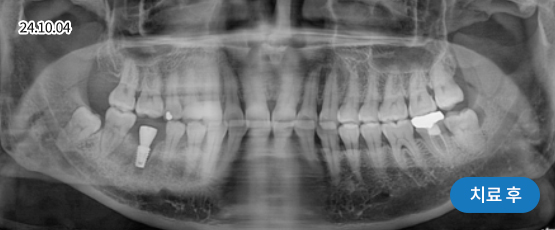

전악 임플란트

치아가 하나도 남아있지 않거나 전체적으로 상실된 경우 추천합니다.

치아의 기능을 다시 회복하기 위해 선택하는 임플란트입니다.

상실한 치아를 오랫동안 방치한 경우 상, 하악 잇몸뼈의 양도 부족한 경우가 많기 때문에 개개인의 건강 상태를 고려하여 정확한 수술 계획을 세워야 합니다.

• 치주질환으로 인해 음식을 씹기 힘들고,

미관도 좋지 않아 치아를 모두 발치한 후

전체 임플란트 수술을 하기로 결정

• 위 8개 + 아래 8개 임플란트 수술 진행 후

위 13개 + 아래 13개 (전체 치아)

임플란트 보철 제작 예정

• 임플란트 보철 완성